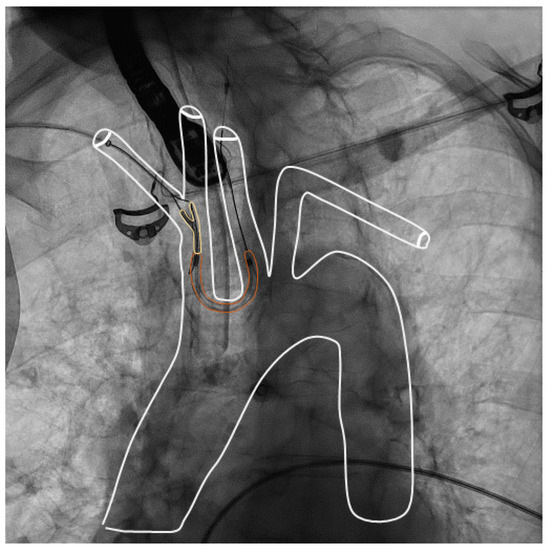

2.2.1. Sentinel Device

2.2.3. LAA Closure Procedure

4.3. Technical Aspects